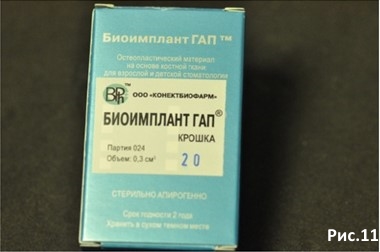

Вскрываем Биоимплант ГАП крошка (ксено – гидроксиапатит) Объём 0,3 см/куб. Рис.11

Биоимплант ГАП крошка Объём 0,3 см/куб = 1100р.